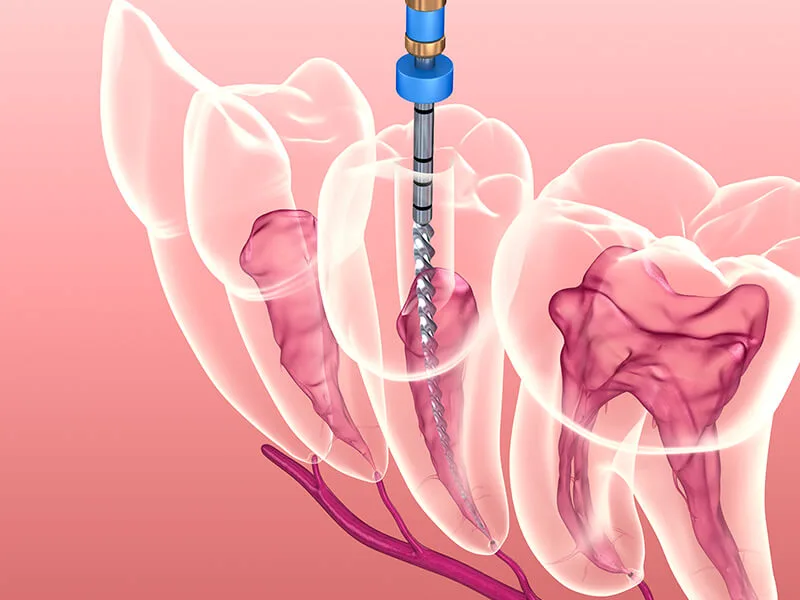

Recursos Técnicos: Uso de tecnologias de diagnóstico por imagem e métodos de desinfecção profunda;

Procedimento Curativo: Limpeza, drenagem (se necessário) e uso de materiais biocompatíveis sob rigorosa biossegurança;